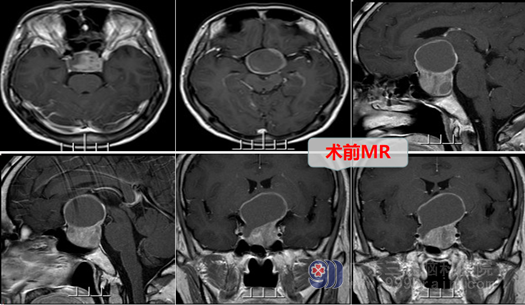

为了进一步的诊治,他来到广东三九脑科医院就诊,被收治到神经外十科,被诊断为鞍区占位: 考虑垂体大腺瘤。外十科欧阳辉主任看着陈先生的磁共振片子对其解释道,由于视神经、视交叉要经过颅内的蝶鞍区,与垂体相近,如果脑垂体长了肿瘤,那么随着肿瘤的长大,就容易对视神经、视交叉造成压迫,从而造成视力下降、视野缺损甚至失明等症状。从陈先生的磁共振结果来看,肿瘤大小已达3.8cm×3.9cm×3.3cm,犹如一颗荔枝的大小。由于受到肿瘤的压迫,视交叉在磁共振影像上是明显受压的。考虑这就是完成陈先生八年来视力下降的原因。